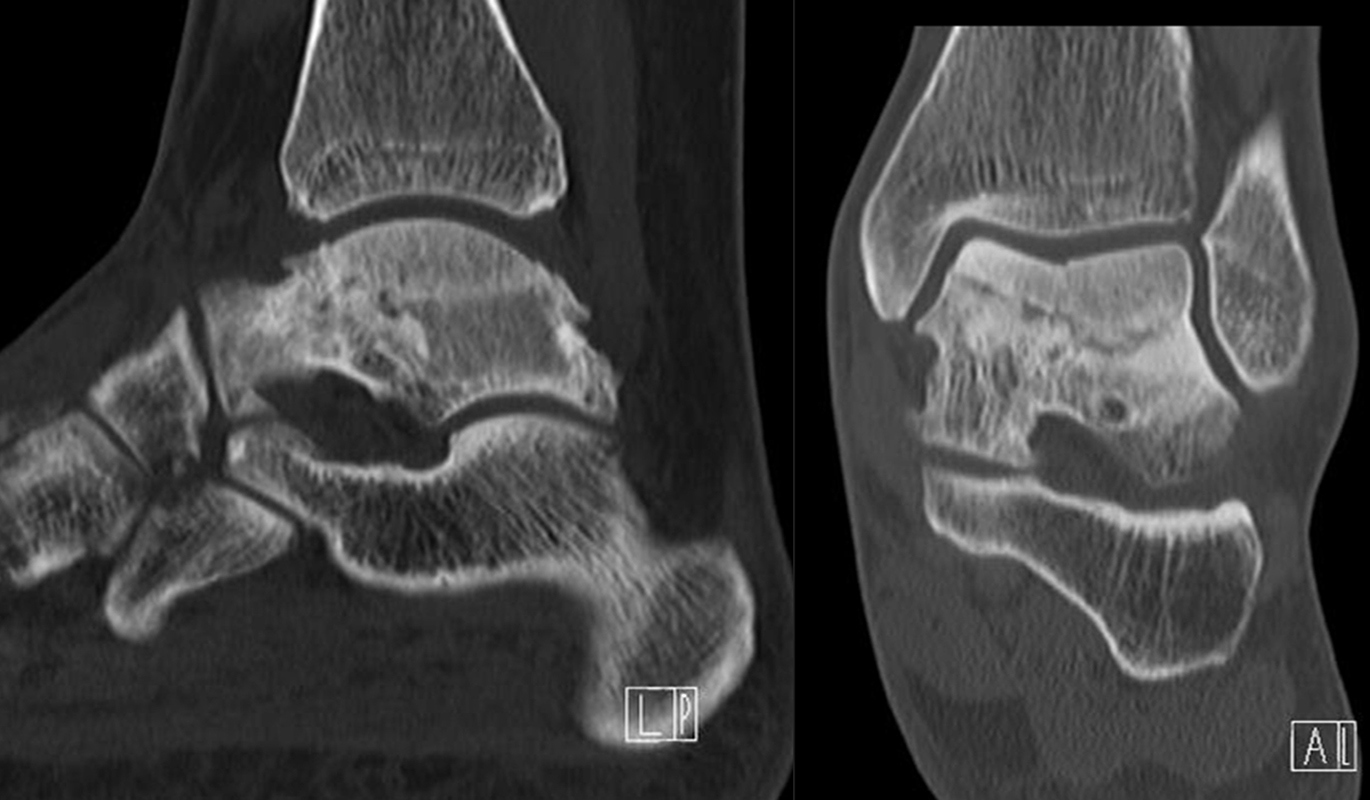

Die Abbildungen 4.2.a bis d zeigen den typischen Aspekt einer talacalcanearen Coalitio. Es besteht nur eine linksseitige, symptomatische Coalitio talocalcaneare (4.2.a und c); das 35 Tage zuvor angefertigte MRT zeigt keine auffälligen Signalveränderungen (4.2.b und d).

Abbildung 4.3. zeigt die Ursache für rechtsseitige Sprunggelenksbeschwerden bei einem Patienten mit talocalcanearen Coalitionen: nur die osteochondrale Läsion an der distalen rechten Tibia ist die Ursache des Schmerzes. Die bilateralen talocalcanearen Coalitionen sind asymptomatisch.